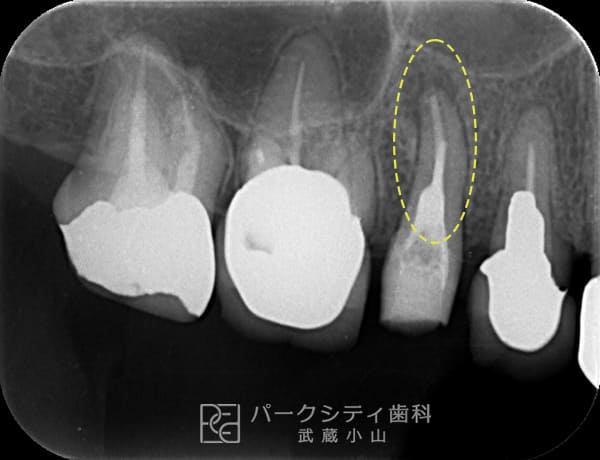

術前

- 主訴

- 歯茎がたまに腫れる

- 治療法

- 根管治療

- 治療期間

- 1か月

- 費用

- 保険治療

慢性根尖性歯周炎の症例です。根管治療をして改善しました。1年経過後も予後が良好です。